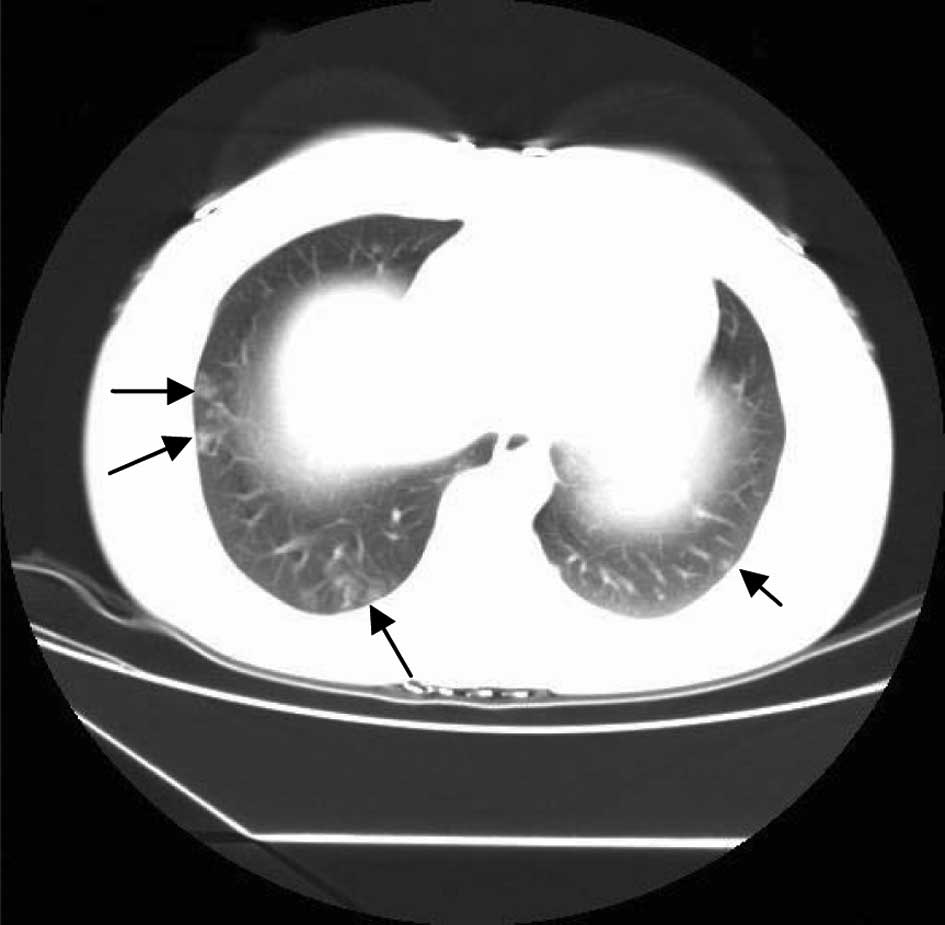

The patient experienced vaginal bleeding at 16 weeks, and repeated TVS revealed 2 viable fetuses; however, 1 placenta was found to be cystic (Fig. 1). Serum hCG levels were found to be elevated at 800,842 mIU/ml. Following careful consideration, the couple decided to terminate the pregnancy and delivery was induced with rivanol. After 37 h, 2 fetuses (230 and 249 g), a normal placenta (200 g) and a partial cystic placenta (290 g) were delivered. Histological examination confirmed the clinical impression of 1 normal placenta and a second partial HM (69, XXY). Three weeks following curettage, serial serum hCG concentrations increased continually, and TVS indicated that the trophoblast had invaded the uterine myometrium. An X-ray computed tomography (CT) chest scan indicated that the trophoblast had metastasized (Fig. 2). Following 3 cycles of chemotherapy consisting of fluorouracil (5-Fu) (26 mg/kg/day, 8 day/cycle) and dactinomycin (KSM) (6 ug/kg/day, 8 day/cycle), the metastases disappeared and hCG levels became negative, remaining normal for 1 year (Fig. 3).

Figure 2

CT chest scan showing the lung metastasis of the trophoblast. Arrows indicate metastatic tumors. CT, computed tomography.